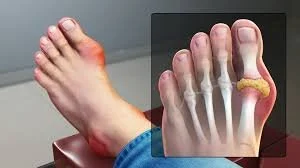

Hammertoes are the most common lesser toe deformity. They make up nearly 50% of all forefoot surgeries.